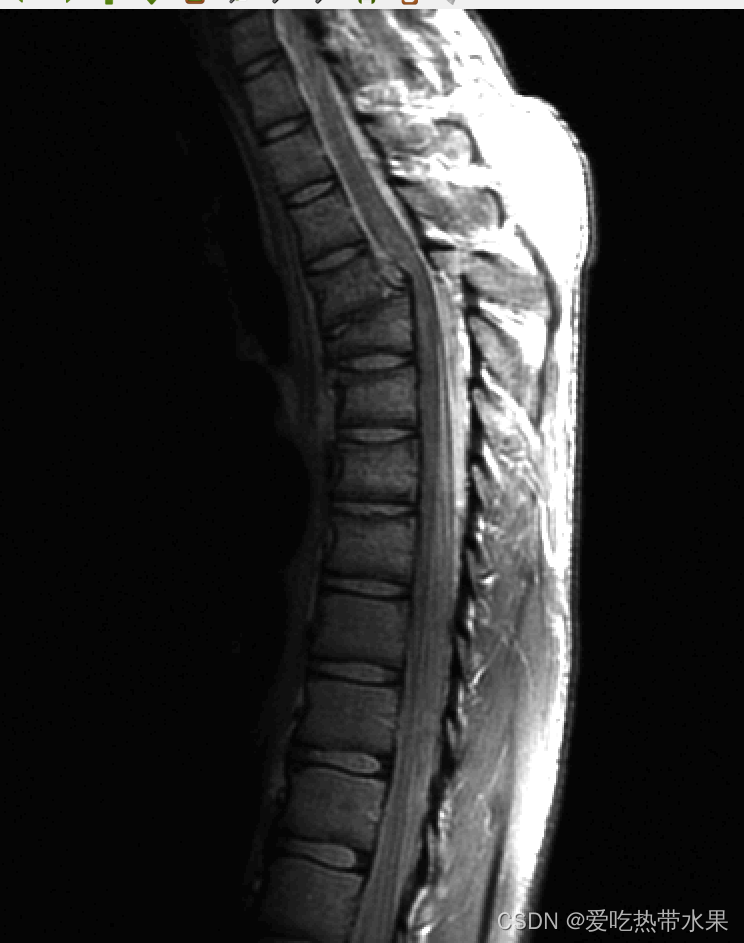

cv::Mat readImg = cv::imread("Fig0308(a)(fractured_spine).tif");

cv::cvtColor(readImg, image1_gray, COLOR_BGR2GRAY); //灰度化

for(int i = 0; i < image1_gray.rows; i++)

{for(int j = 0; j < image1_gray.cols; j++){int value1 = (int)image1_gray.at<uchar>(i , j);value1 = value1 / 255;value1 = value1 * value1 * value1 *255;image1_gray.at<uchar>(i , j) = value1;}}cv::imshow("image",image1_gray);cv::waitKey(0);

整体变暗.jpg |

//c = 1 y = 0.7 时图像变亮

//opencv + qt

#include

cv::Mat image1_gray; //灰度图

{for(int j = 0; j < image1_gray.cols; j++){image1_gray.at<uchar>(i, j) = qPow(image1_gray.at<uchar>(i, j), 0.7);}

}

cv::normalize(image1_gray, image1_gray, 0 , 255, NORM_MINMAX);

cv::imshow("image",image1_gray);

cv::waitKey(0);

整体变亮.jpg | 原图.jpg |